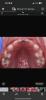

Девочки,7 Зубов пролечили..

Пожалуйста,самую лучшую зубную пасту посоветуйте мне 🥹

Представьте,в три года 7 зубов 🥲🥲🥲